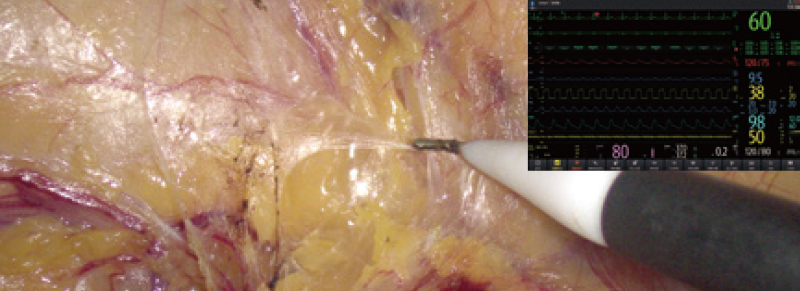

C├Īmara

Captura im├Īgenes del campo quir├║rgico y panor├Īmicas

Sistema de endoscop├Ła

- Las im├Īgenes quir├║rgicas de endoscopios, campos operatorios, monitores y c├Īmaras panor├Īmicas se transmiten en tiempo real a distintas ubicaciones, lo que facilita el intercambio fluido de las condiciones quir├║rgicas entre los miembros del equipo quir├║rgico.